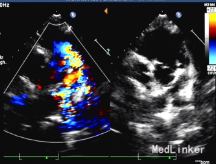

内脏、心房正位,心脏于左前胸探及,心尖指向左下。肝脏位于右上腹,肝静脉、下腔静脉回流入右心房,脾、胃位于左上腹,肺静脉回流入左心房。心室右袢,房室连接一致,二尖瓣、左室位于左侧与左房连接,三尖瓣、右室位于右侧与右房连接。主动脉增宽,前移骑跨于室间隔之上,骑跨率约50%。右室流出道内径为0.8厘米,肺动脉瓣环径为1.4厘米,主肺动脉内径1.8厘米,左右肺动脉分支内径分别为1.0厘米、1.1厘米,肺动脉瓣增厚、回声增强,收缩期右室流出道至肺动脉腔内血流速度增快,峰值速度为5.2米/秒,压差108毫米汞柱。大动脉水平未见明显分流信号。右位主动脉弓。主动脉瓣下室间隔回声连续中断,缺损径:2.1厘米,左室和右室血流射入主动脉。房间隔回声连续完整。右房、右室饱满,左房、左室不大。左室舒张末期容积(EDV)45毫升。二、三尖瓣回声活动正常。